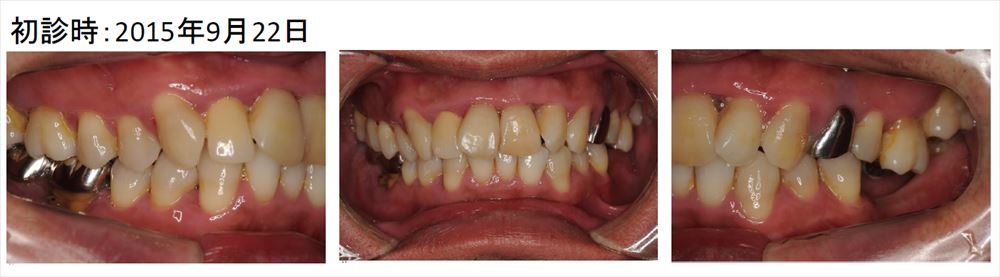

この症例の患者さまは歯茎からの膿に悩み他院から転院してきた方です。

この様に歯茎は前歯も奥歯も真っ赤で白い膿が出ています。

こちらはメンテナンス時です。初診と比較し歯茎の色が良くなりました。歯茎も引き締まっていますね。